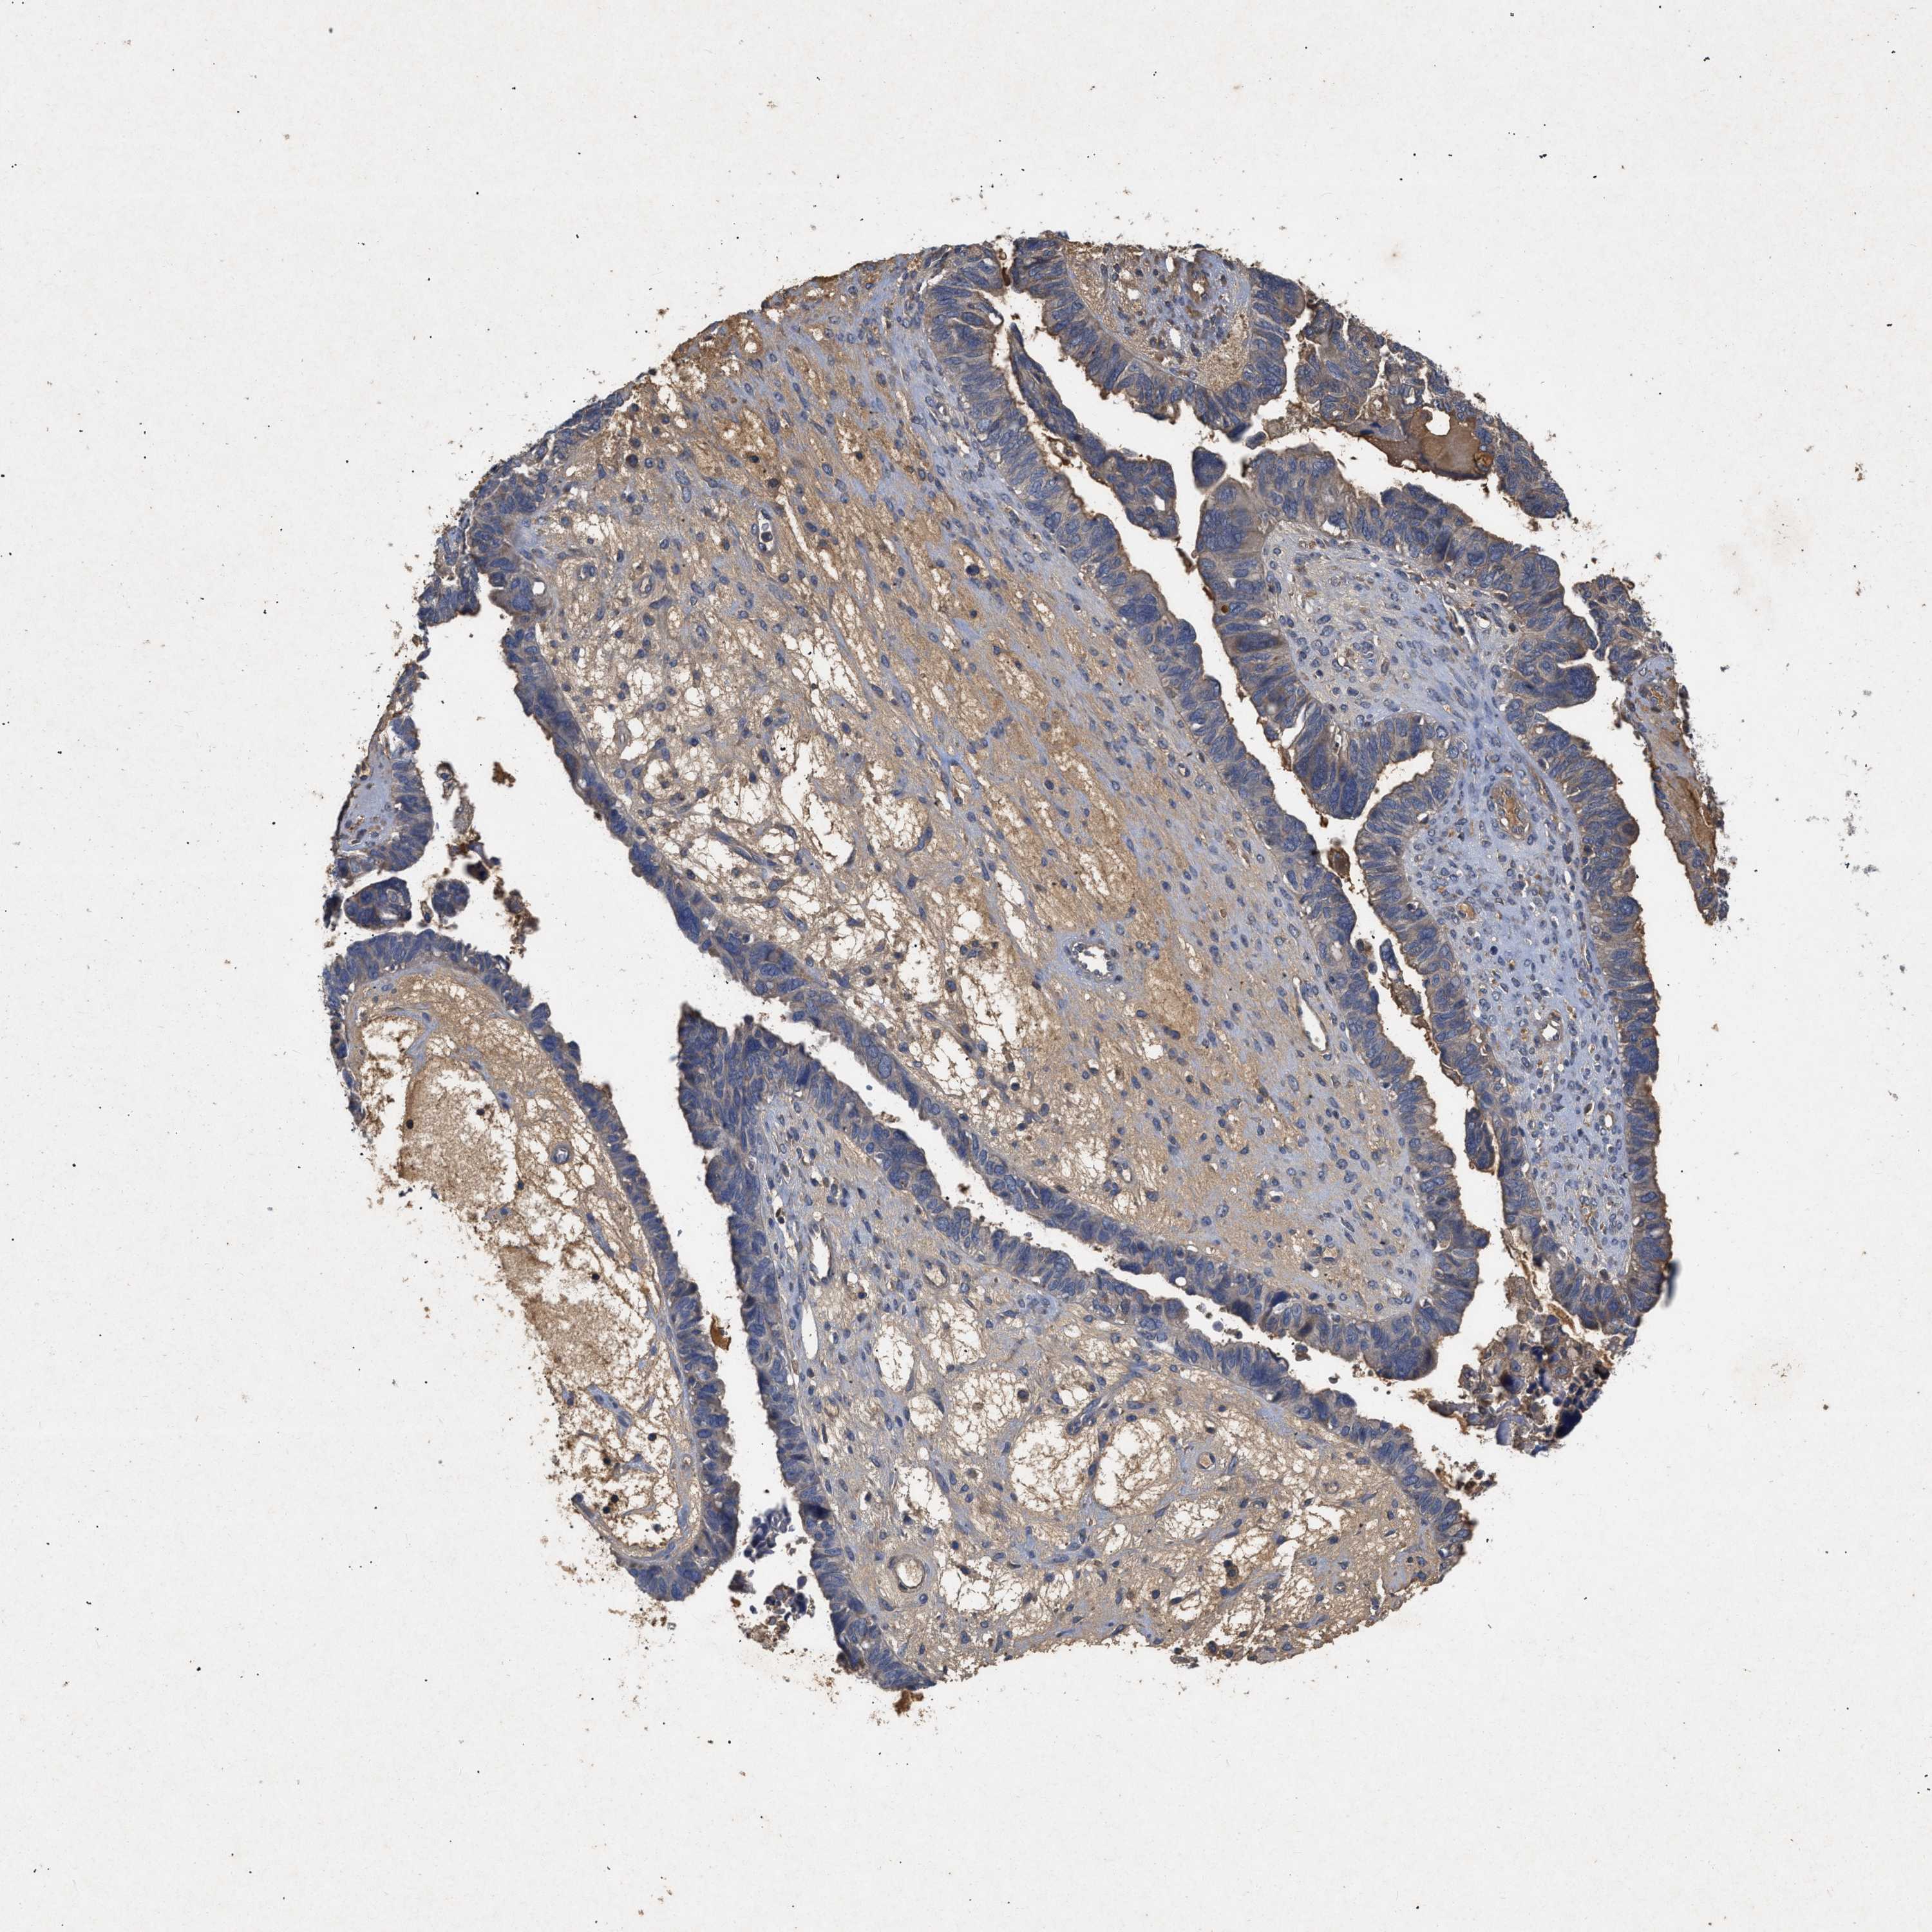

OVARIAN CANCER - Protein expressioni

A mouse-over function shows sample information and annotation data. Click on an image to view it in a full screen mode. Samples can be filtered based on level of antibody staining by selecting one or several of the following categories: high, medium, low and not detected. The assay and annotation is described here.

Note that samples used for immunohistochemistry by the Human Protein Atlas do not correspond to samples in the TCGA dataset.

Antibody stainingi

Antibody staining in the annotated cell types in the current human tissue is reported as not detected, low, medium, or high, based on conventional immunohistochemistry profiling in selected tissues. This score is based on the combination of the staining intensity and fraction of stained cells.

Each image is clickable and will lead to virtual microscopy that enables deeper exploration of all samples and also displays staining intensity scores, fraction scores and subcellular localization as well as patient and tissue information for each sample.

Antibody CAB034411

Cystadenocarcinoma, mucinous, NOS

Cystadenocarcinoma, serous, NOS